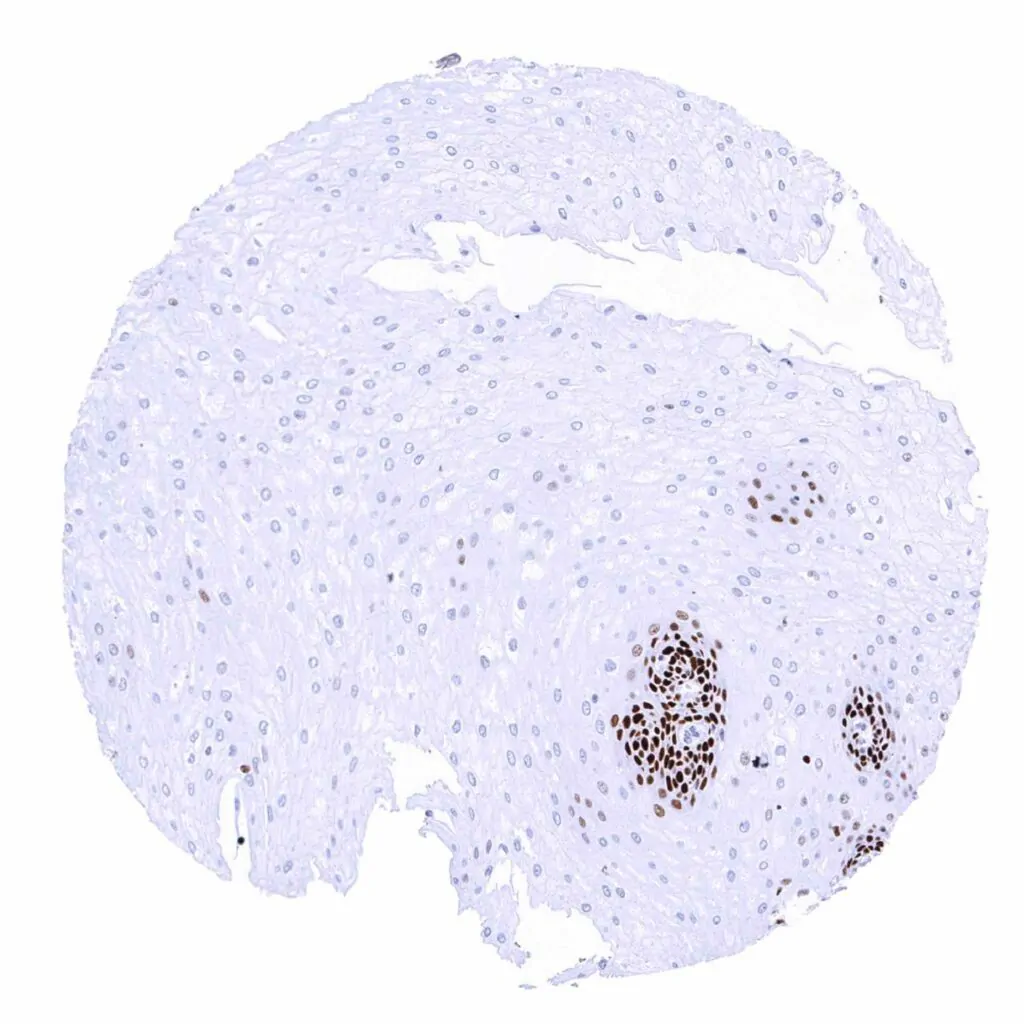

Lymph node – Many lymphocytes are MCM2 positive. Strongest MCM2 staining occurs in most cells of germinal centres and in scattered individual cells of the interfollicular zone